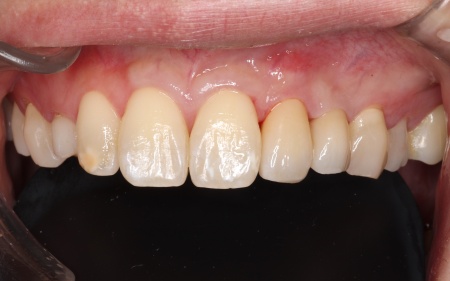

30代男性 歯が欠損した部分を片側固定ブリッジで補った症例

「大人になってからも残っていた乳歯が抜けてしまったので、歯を入れたい」とご相談いただきました。

拝見したところ、左上の糸切り歯が欠損していました。

これまでは乳歯が残っていたものの、最近になって自然に抜けてしまったとのことです。

レントゲン検査で詳しく調べた結果、患者様は生まれつき左上の糸切り歯の永久歯が存在しないことが分かりました。

被せ物の素材は患者様と相談のうえ、自然な白さがあり変色や劣化が起こりにくいセラミックを選択しました。

まず手前の歯を削って土台を作り、精密な型取りを行います。

後日、完成したブリッジを装着し、噛み合わせなどに問題がないかを確認して治療を終了しました。